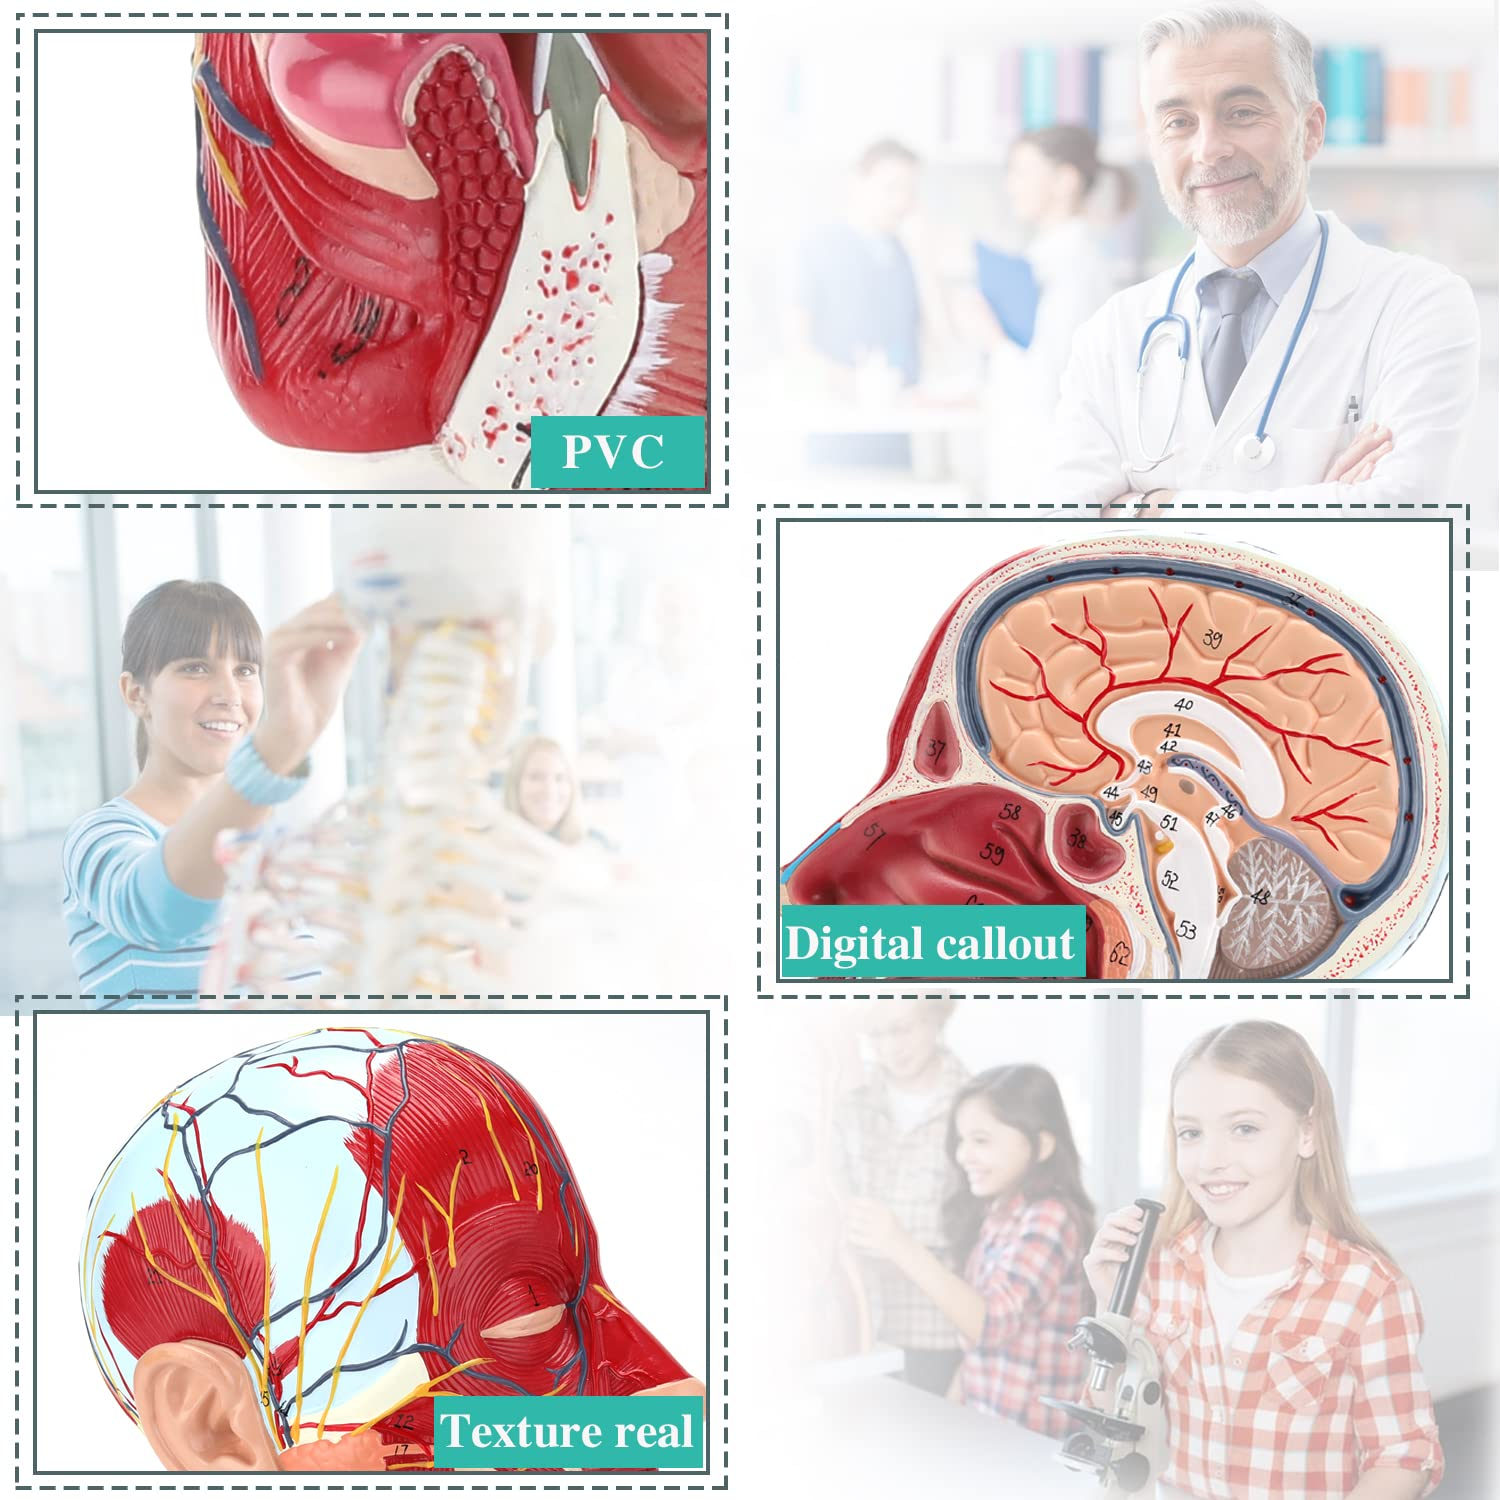

【Ikhwalithi ephezulu】 Imodeli ye-Anatomy yeBrain Anatomy, eyenziwe ngemvelo yemvelo ye-PVC enobuntu, okulula ukuyihlanza. Amamodeli we-anatomy apendwe ngesandla futhi aqoqene ngokunakwa okukhulu ngokuningiliziwe imininingwane.

【Imodeli ye-Neurovascular yemisipha ekhethekile enemininingwane eminingi, izinombolo ezimakwe kakhulu, izindlebe ezivinjelwe, zijulisa ukuqonda kwemisipha engaphezulu, imikhumbi, izinzwa kanye nezinhlaka zangaphakathi zekhanda nentamo. I-Red-artery, i-Blue-Vein, i-Yellow-Nerve.

Izici 【Izici】 Kubonisa izicubu ezingezinhle zobuso obudaluliwe; Imithambo yegazi engekho emthethweni nezinzwa zobuso ne-scalp; Izakhiwo ezingaphakathi ze-Parotid Gland & Upper Respiratory Tract; isakhiwo sesigaba se-sagittal somgogodla wesibeletho.